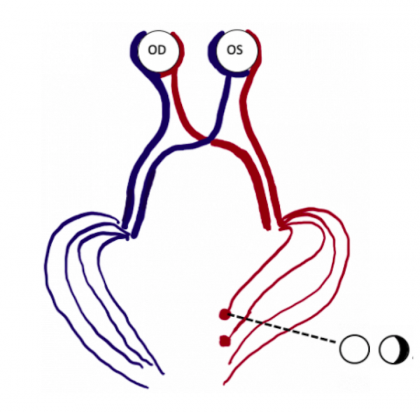

The etiology for this special monocular visual field defect is due to the distribution and overlap of the nasal and temporal visual fields. The normal visual field in degrees from the central point is 60 degrees nasal, 50 degrees superiorly, and 90-100 degrees temporally (Figure 1). The nasal and temporal hemifields in each eye overlap but the monocular temporal crescent has no perimetric correlate in the fellow eye because the temporal visual field is larger than the nasal visual field, hence there are more crossing nasal fibers than there are ipsilateral temporal fibers with a 53:47 ratio. [2] The extra nasal fibers that cross accounts for the non-overlapping contralateral temporal crescent. These fibers end up in the most anterior medial striate cortex and compromise 8-10% of the striate cortex. [3] This monocular representation in a retrochiasmal pathology is attributed to the monocular innervation in that area.[4] Thus, 30-40 degrees of the peripheral temporal visual field is unpaired and has unilateral representation in the contralateral visual cortex. Damage to this area of the visual cortex leads to the contralateral temporal crescent (Figure 2.)[5][6]

Any patient presenting with a monocular temporal crescentic visual field defect should have a full neuro-ophthalmic and ocular exam to exclude intraocular causes of the visual field loss (e.g., retinal detachment). A relative afferent pupillary defect (RAPD) is generally present in such cases ipsilateral to the retinal or optic nerve lesion, whereas in a unilateral missing temporal crescent there is no RAPD. It has been shown that a quick test can be used by the examiner by moving their hand slowly behind the patient's head, anteriorly, showcasing that the temporal visual field border extends beyond 90 degrees. Confrontation visual field testing may be helpful in documenting the peripheral crescentic field loss. The test can be used to detect constriction of the temporal aspect of the visual field but may not include all of the temporal peripheral field because the examiner’s hand is not long enough to enter the temporal crescent out of the blind area.[7]